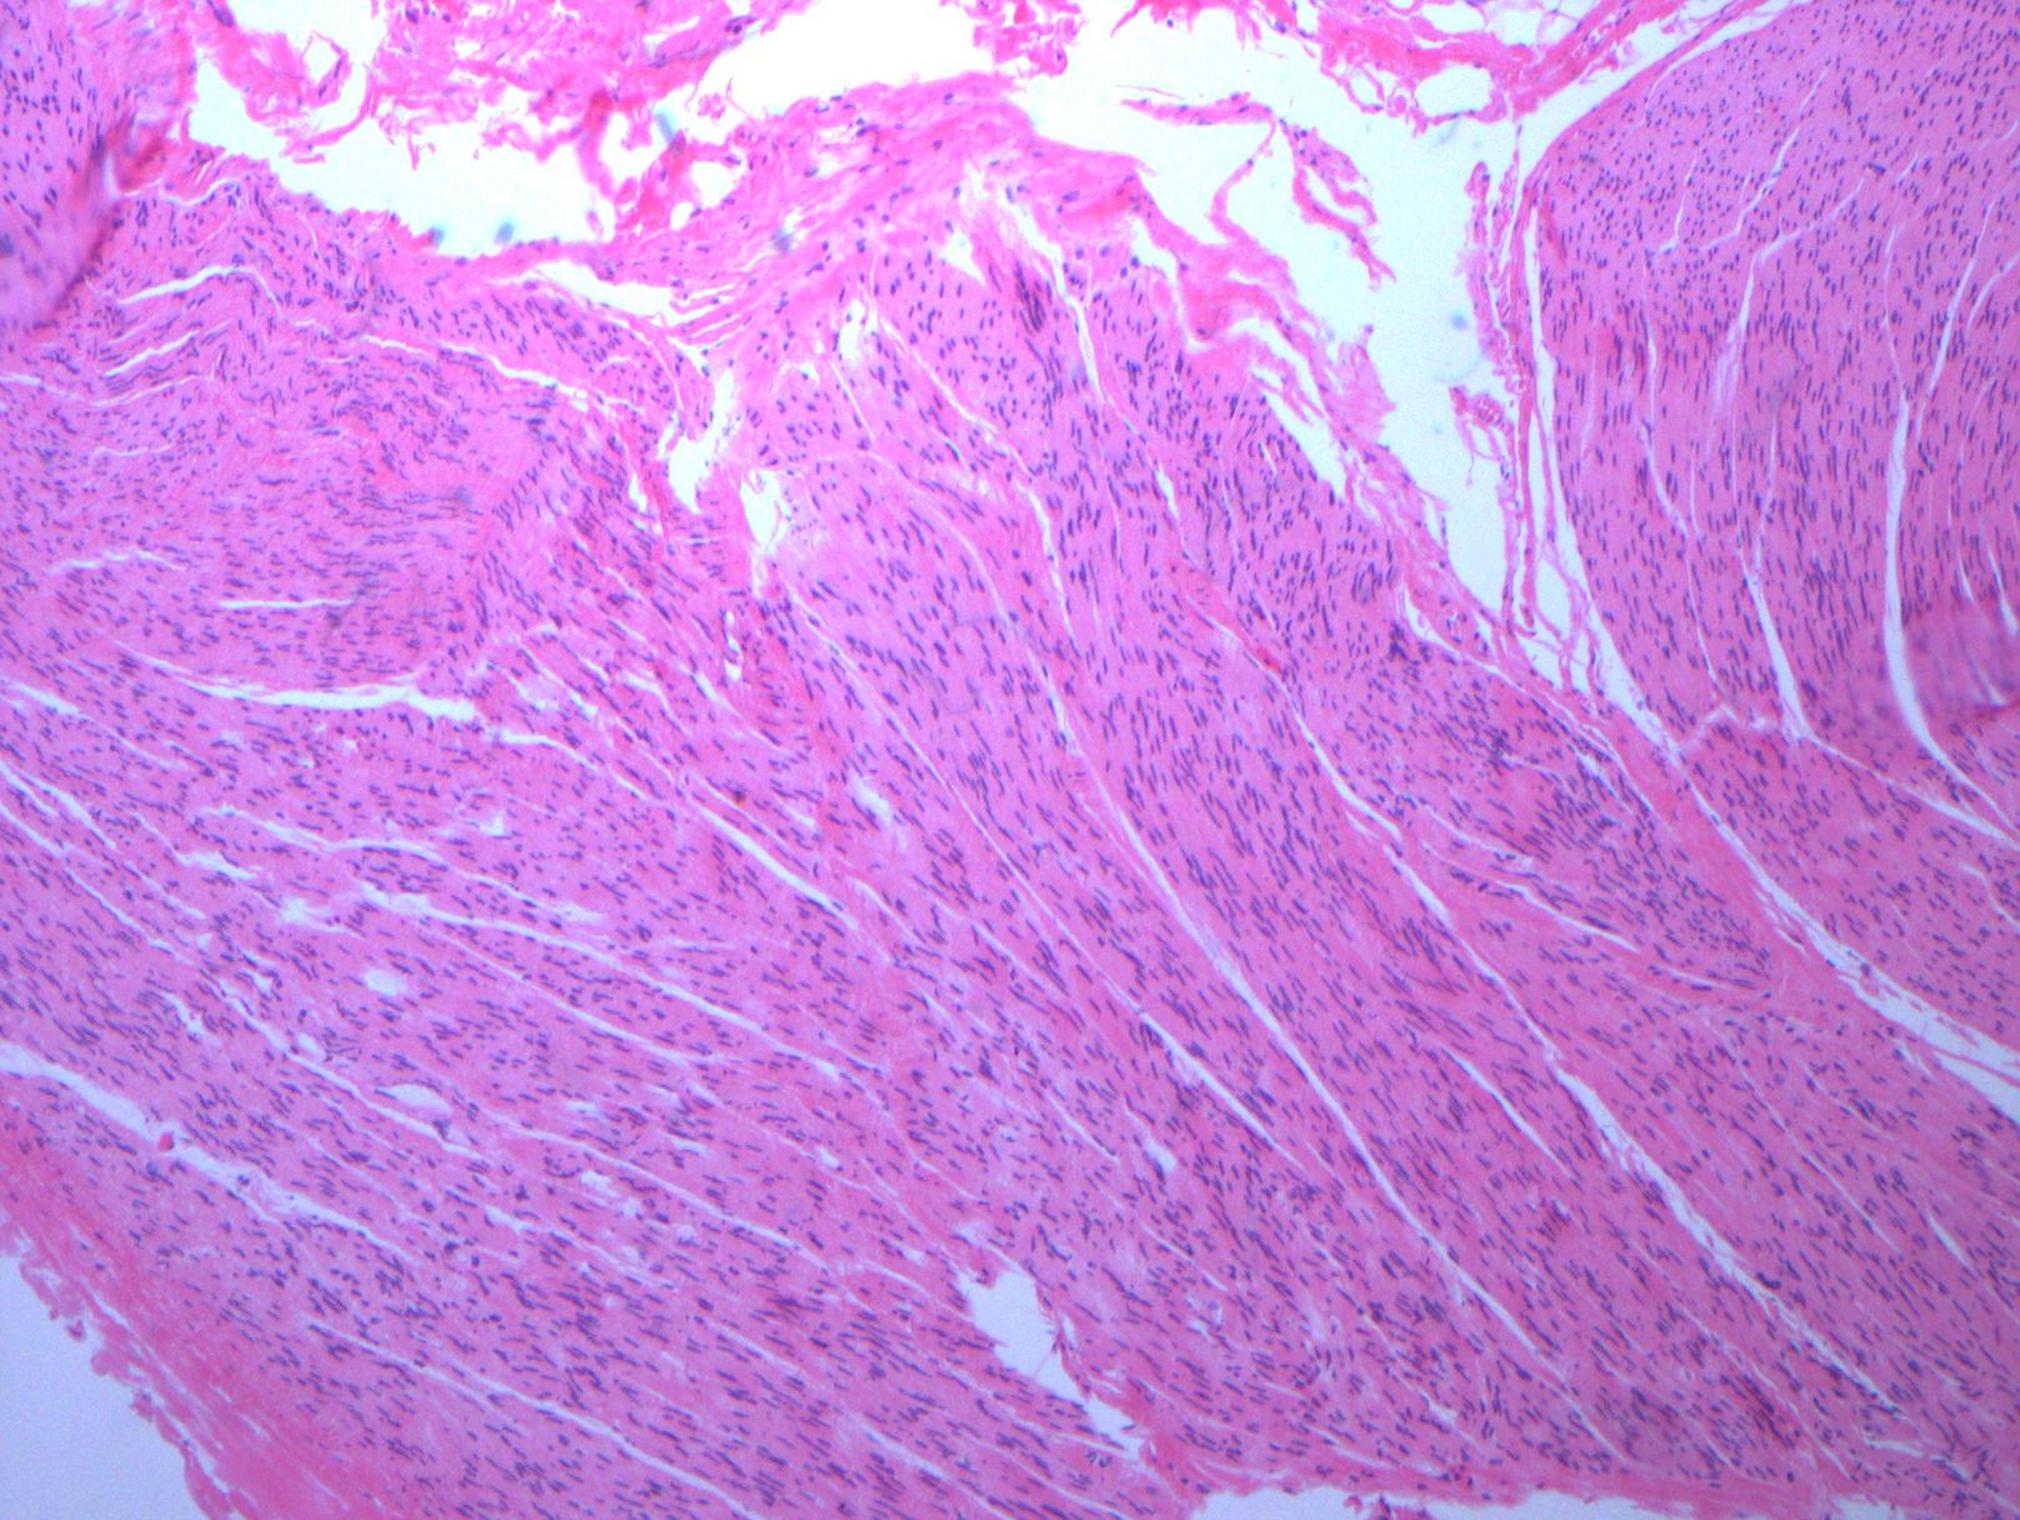

Tissue from a MAL release (median arcuate ligament) is nerve

This was removed during a laparoscopic median arcuate ligament release. It was a hard white band compressed under the ligament and itself compressing the celiac axis. During the release, I grabbed a piece of these fibers and sent it for pathology under the preliminary diagnosis of celiac plexus, and it was. Described as “typical for a peripheral nerve…mostly Schwann cell nuclei in between nerve fiber.” Other micrographs in the specimen had ganglionic fibers but our pathologist wasn’t able to locate it. This is an important piece of the pathoanatomy because I believe that this is the nidus of the pain associated with median arcuate ligament syndrome, not a regional ischemia that can only occur if the celiac axis is an end artery, which can really only happen after a major exenteration like a Whipple procedure.